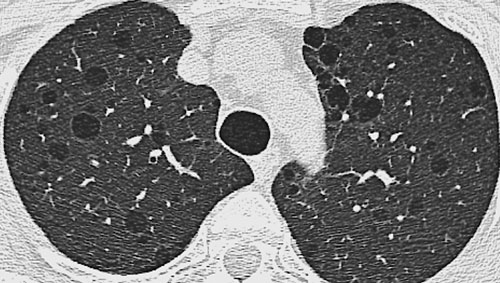

HRCT - Basic Interpretation